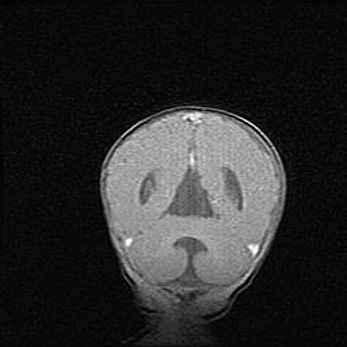

Множественные кисты обоих полушарий головного мозга, наибольшая из них в правой затылочной области. Ассиметричная атрофическая гидроцефалия.

Возраст: 7 месяцев

Вес: 5660 г

Пол: мужской

Окружность головы: 41,5 см

Срок гестации: 28-29 недель

Кисты головного мозга развиваются в результате многоочаговых некрозов вещества мозга и возникают вследствие перенесенной перинатальной инфекции, менингитов, энцефалитов, асфиксии, родовой травмы, расстройств мозгового кровообращения различного генеза. Образованию кист в веществе головного мозга плодов и новорожденных способствуют такие факторы, как высокое содержание в нем воды, недостаточная (или отсутствие) миелинизация и слабая астроглиальная реакция на повреждение.

Кисты могут сочетаться с гидроцефалией и другими поражениями головного мозга.